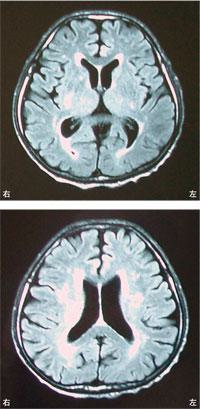

75歳の男性。高血圧と糖尿病の治療を長期にわたり行っている。徐々に歩行障害がみられるようになり、転倒することが多くなった。頭部MRIを示す。この患者で認められないと考えられるのはどれか。

左側弛緩性麻痺

65歳の男性。右利き。脳梗塞による片麻痺。Brunnstrom法ステージは上肢、手指、下肢ともにⅢ。回復期リハビリテーション病棟では車椅子で移動している。発症後3か月の頭部MRIを示す。この患者が基本動作練習を開始した際に観察されるのはどれか。

座位練習で右手を支持に使うことができない。

車椅子駆動の際に廊下の左壁によくぶつかる。

練習を繰り返しても装具装着の手順を間違える。